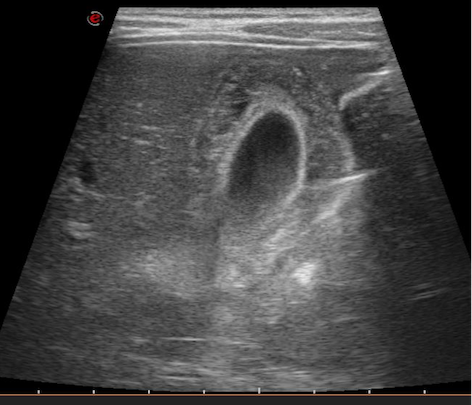

Nel sospetto di appendicite si esegue un’ecografia dell’addome (Figura 1), che però nega tale sospetto, ma evidenzia una colecisti a pareti inspessite senza calcoli nel lume con raccolta peri-colecistica settata di circa 6 mm; lieve splenomegalia.